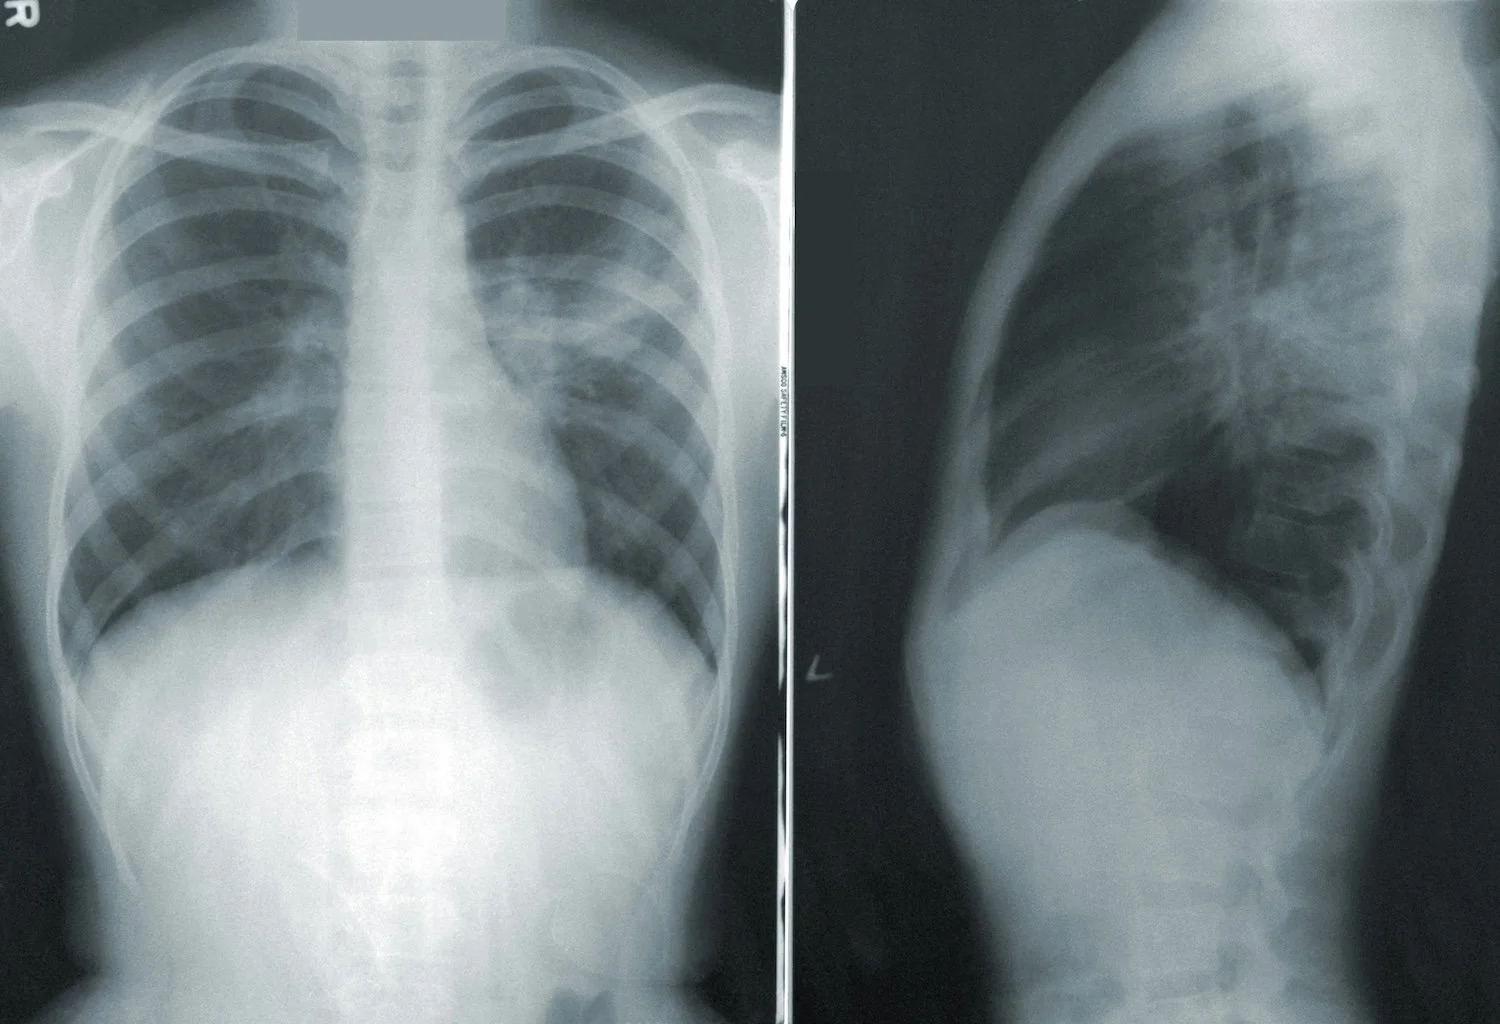

An x-ray showing pneumonia (via CDC)

Pneumonia can be diagnosed through listening to your lungs, blood tests, chest x-rays, measuring oxygen levels, and/or by sampling the fluid in your lungs – in addition to screening for symptoms like: